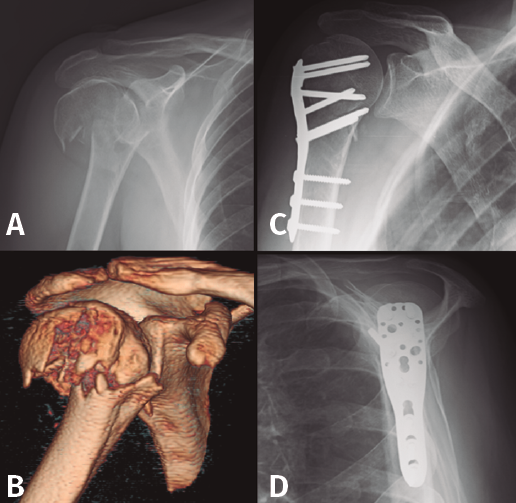

Es probablemente el tratamiento más usado en este tipo de fracturas, normalmente con placas con tornillos de bloqueo poliaxiales en cabeza y tuberosidades, y con tornillos corticales en diáfisis (Figura 3). El uso de suturas irreabsorbibles para mantener la reducción de las tuberosidades también representa un método aceptado para tratar estas fracturas, junto con la placa, las agujas de Kirschner o los clavos de Rush o Ender(9,10), ya que la buena calidad ósea del paciente joven permite un correcta estabilidad de los fragmentos y disminuye la agresividad del procedimiento.

Figura 3. Evolución radiológica de una osteosíntesis con placa de una fractura de húmero proximal derecho. A: radiología simple anteroposterior preoperatoria; B: tomografía computarizada preoperatoria; C y D: evolución radiológica del tratamiento.